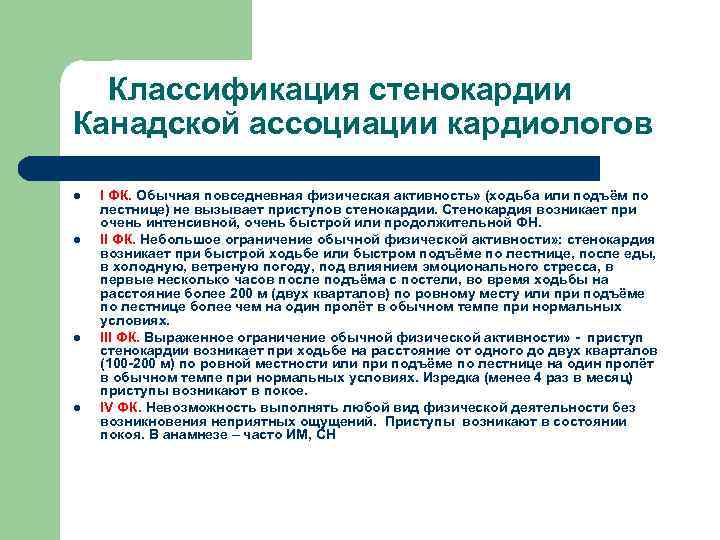

Классификация стенокардии Канадской ассоциации кардиологов l l I ФК. Обычная повседневная физическая активность» (ходьба или подъём по лестнице) не вызывает приступов стенокардии. Стенокардия возникает при очень интенсивной, очень быстрой или продолжительной ФН. II ФК. Небольшое ограничение обычной физической активности» : стенокардия возникает при быстрой ходьбе или быстром подъёме по лестнице, после еды, в холодную, ветреную погоду, под влиянием эмоционального стресса, в первые несколько часов после подъёма с постели, во время ходьбы на расстояние более 200 м (двух кварталов) по ровному месту или при подъёме по лестнице более чем на один пролёт в обычном темпе при нормальных условиях. III ФК. Выраженное ограничение обычной физической активности» - приступ стенокардии возникает при ходьбе на расстояние от одного до двух кварталов (100 -200 м) по ровной местности или при подъёме по лестнице на один пролёт в обычном темпе при нормальных условиях. Изредка (менее 4 раз в месяц) приступы возникают в покое. IV ФК. Невозможность выполнять любой вид физической деятельности без возникновения неприятных ощущений. Приступы возникают в состоянии покоя. В анамнезе – часто ИМ, СН